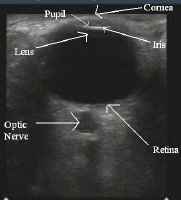

What imaging is quick, done at bedside and is 100% sensitive and 97% specific compared to exam and CT?

•Can Dx scleral and choroidal lacerations, vitreous hemorrhage, retinal detachment, radiolucent and radio-opaque FB, retrobulbar hematomas

When should this imaging NOT be used?

ULTRASOUND

ø Contraindicated in large globe lacerations